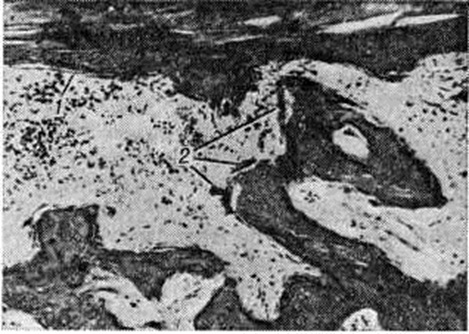

Рис. 4.

Микропрепарат диафиза плюсневой кости выше уровня демаркации после отморожения IV степени: 1— остатки компактного вещества; 2— остеокласты в лакунах; окраска гематоксилин-эозином; × 120.

При отморожении III и IV степени после развития реактивных процессов формируются три зоны: тотального некроза, демаркационного воспаления, восходящих дистрофических и очаговых некротических изменений (рисунок 2). Наиболее глубокие изменения локализуются обычно в дистальных участках конечности. Однако может иметь место и гнездное расположение очагов деструкции, когда участки некроза располагаются также в проксимальных отделах конечности (цветной рисунок 6). Зона тотального некроза формируется после полного прекращения кровообращения, когда некротизированные ткани подвергаются мумификации (смотри полный свод знаний) с исходом в сухую гангрену (рисунок 3, а). Гистологический исследование обнаруживает отсутствие ядер в клетках, наличие бесклеточных гомогенных лент коллагеновых пучков в дерме, превращение сарколеммы мышечных волокон в однородную или глыбчатую массу. Просветы сосудов щелевидные или заполнены склеенными кровяными клетками и тромбами. Если проходимость кровеносных сосудов сохраняется или восстанавливается, развивается влажная гангрена (смотри полный свод знаний). При этом лейкоциты проникают в участки некроза (смотри полный свод знаний), которые затем расплавляются ферментами, освобождающимися при разрушении лейкоцитов. Гнилостные микробы могут значительно усилить эти процессы. При влажном некрозе (рисунок 3, б) эпидермис отслоен, ткани отёчны, диффузно инфильтрированы лейкоцитами, на поверхности и в глубине обнаруживаются скопления микробов, а нередко и грибков.

Зона восходящих дистрофических и очаговых некротических изменений формируется проксимальнее зоны демаркационного воспаления. Она не имеет чётких границ из-за отсутствия видимых невооруженным глазом изменений кожных покровов. Дистрофические, некротические и вторичные воспалительные процессы обнаруживаются здесь только при микроскопическом исследовании. Если после Отморожение длительно сохраняются расстройства микроциркуляции или возникают нарушения кровообращения воспалительного характера, дистрофические и некротические процессы могут нарастать, распространяясь проксимальнее зоны демаркационного воспаления. В костной ткани выше границы демаркации происходят процессы перестройки в виде остеокластической резорбции (рисунок 4) и новообразования костных перекладин пролиферирующими остеобластами. В дальнейшем в артериях и венах обнаруживается склероз стенок, разрастание внутренней оболочки и организация тромбов, что приводит к сужению просвета сосудов (рисунок 5). Развиваются невриты (смотри полный свод знаний), которые морфологически проявляются разрастанием аксонов в виде невром, пролиферацией эндоневрия и периневрия.